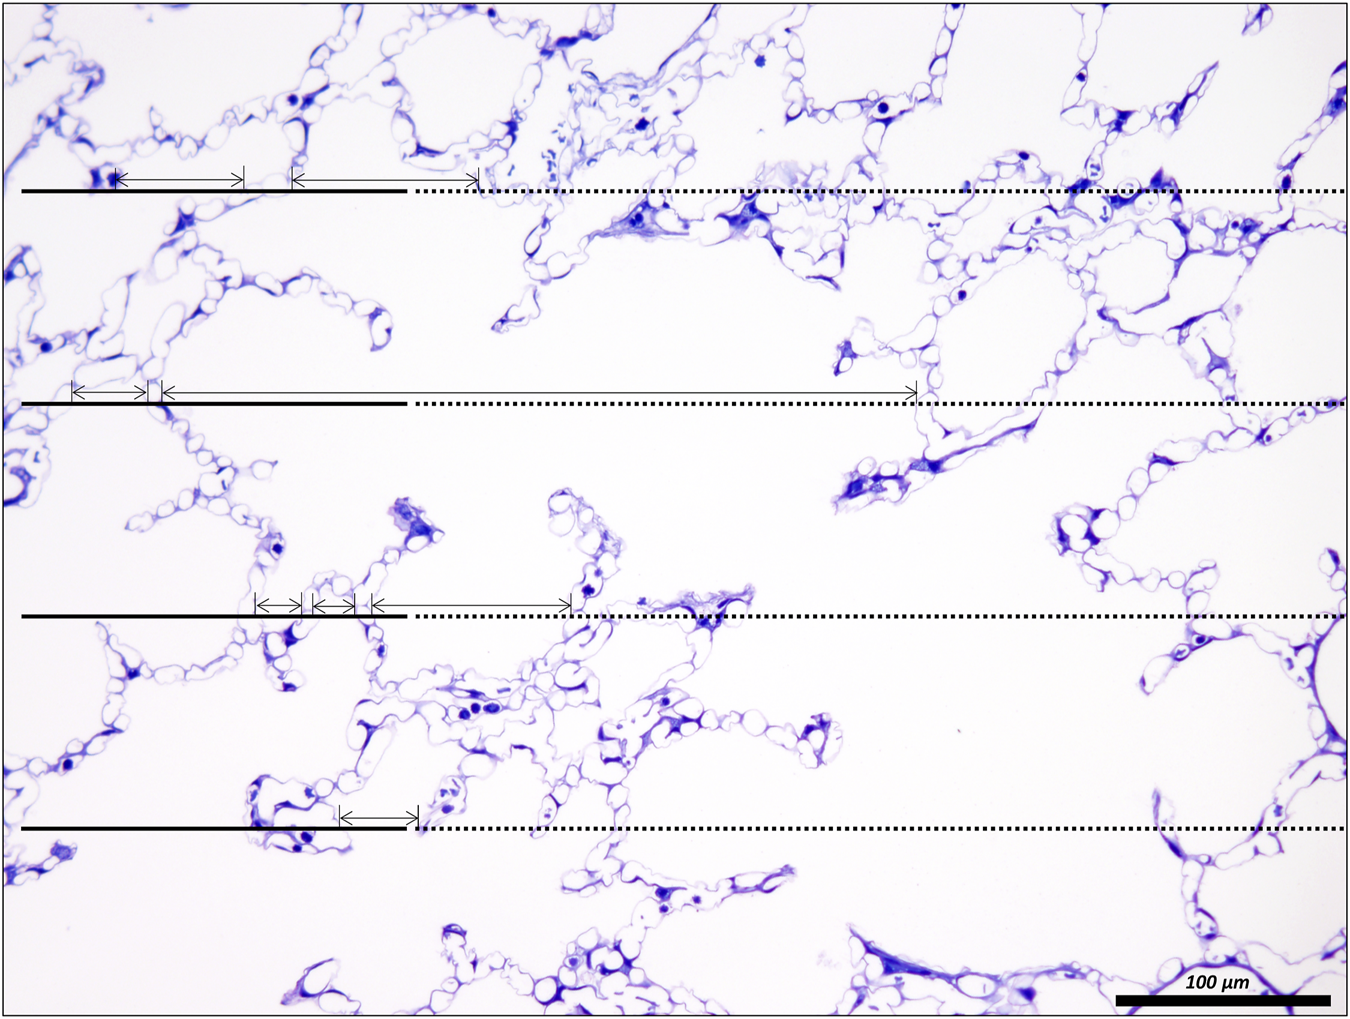

The acinar airspaces are subject to cyclic volume changes during respiration. In three-dimensional datasets from, e.g., micro computed tomography or synchrotron-based imaging, appropriate image processing protocols can segment acini and compute their surface area and air volume semi-automatically (Vasilescu et al., 2012; Haberthür et al., 2021). These data provide valuable information on deformation when determined at different levels of inflation or (preferably) dynamically during ventilation (Cercos-Pita et al., 2022). Using two-dimensional images, which are oftentimes more readily obtainable, an efficient and easy tool to investigate the dimensions of the acinar airspaces is the determination of chord lengths (= linear intercept length), which are randomized, linear measurements from one boundary of the acinar airspace to the next (Knudsen et al., 2010). Although it is an one-dimensional parameter describing a complex three-dimensional anatomical structure, it can easily be determined with the help of test-lines projected on the randomized fields of view (Figure 5). An advantage is that chord length measurements also provide information of lung function in terms of the free path of oxygen to the alveolar wall as well as airspace heterogeneity occurring with different lung volumes. The chord length of acinar airspaces correlates well with the apparent diffusion index of hyperpolarized helium determined with magnetic resonance tomography (MRI) (Woods et al., 2006), an in vivo measurement that also gives information on regional mechanics and microarchitecture (Choy et al., 2010). Chord length measurements can be performed with non-destructive imaging including micro computed tomography as well as MRI (Chan et al., 2021). In healthy lungs and early bleomycin-induced acute lung injury fixed in vivo at stable airway pressures of 10 or 1 cmH2O on expiration (Lutz et al., 2015; Knudsen et al., 2018), the distribution plots of chord lengths are comparable at low lung volumes (Figure 6). With higher lung volume the heterogeneity of chord lengths increases, a pattern which is more pronounced in lung injury. The most frequently observed intercept length (peak of the histogram) is shifted to the right (larger lengths) in the injured compared to the healthy lungs. Also, a second peak is unmasked in the injured but not in the healthy lung in the range of 150 µm. Thus, the dimensions of the acinar airspaces become more heterogeneous in injured lungs at higher pressures although at that very early timepoint after bleomycin the injury is subtle. These observations in the distribution of chord lengths might indicate abnormalities in acinar micromechanics resulting in increased ventilatory heterogeneity, a mechanism which has been discussed to contribute to ventilation-induced lung injury (VILI) via mechanical stress (Albert et al., 2019; Nieman et al., 2020).

FIGURE 5. Unbiased test-system for measurements of chord length of acinar air spaces. A healthy rat lung was fixed in vivo by vascular perfusion via the vena cava caudalis at an airway opening pressure of 5 cmH2O on expiration after two recruitment maneuvers (3 s pause at 30 cmH2O) (Knudsen et al., 2018). The parameter “chord length” is also known as the linear intercept length. It is based on simple, linear measurements of the dimension of the acinar airspaces from one border to the next. The left side of the randomly sampled image contains four straight line-segments, extended to the right by a dashed line, the so-called guard line. The line segments on the left serve to sample the starting point of the measurements. Each time the line segment intersects an interalveolar septum a measurement is performed from the intersection to the next surface of an interalveolar septum. The direction of the measurement follows the run of the test line and if needed also the dashed guard line. In order to locate the points of measurements exactly the top border of the line segment is used. The arrows label the measurements in this example. Some measurements are performed within an alveolus, others, however, travers via the alveolar opening through the alveolar duct airspace to the other side so that these measurements encompass both alveolar and alveolar duct airspaces.